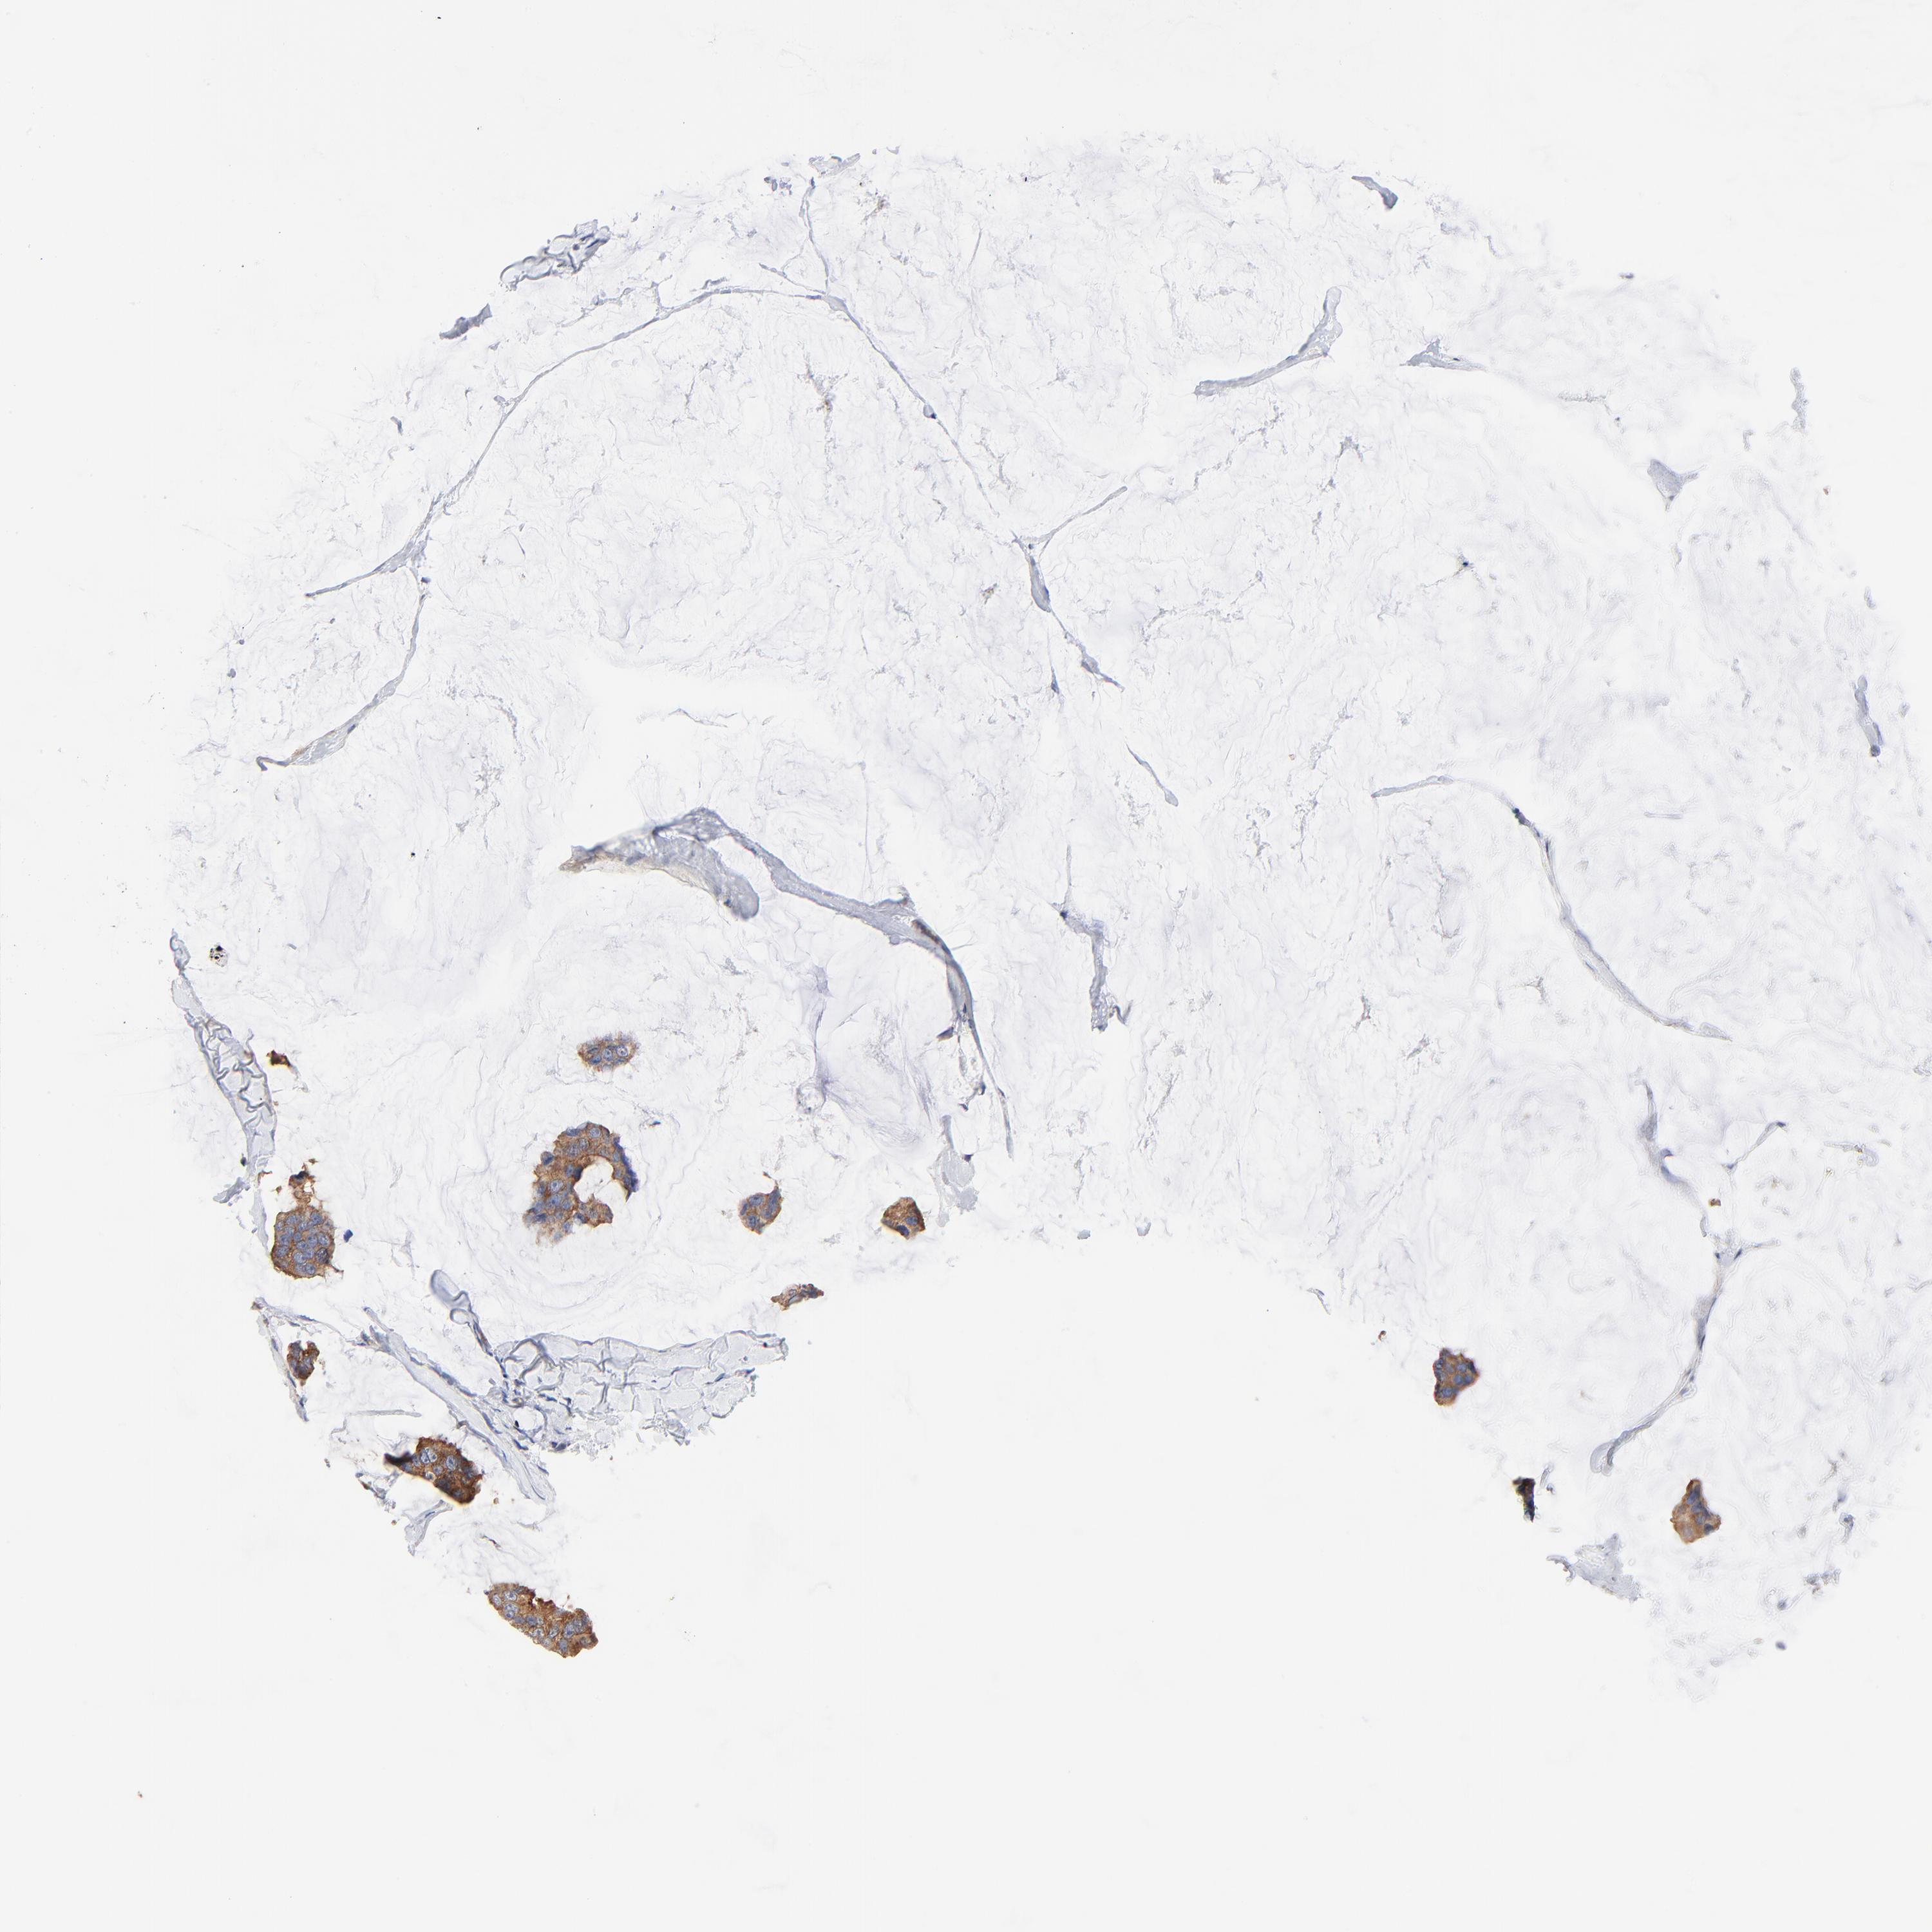

CANCER BREAST CANCER Show tissue menu

BRCA TCGA BRCA VALIDATION PROTEIN EXPRESSION